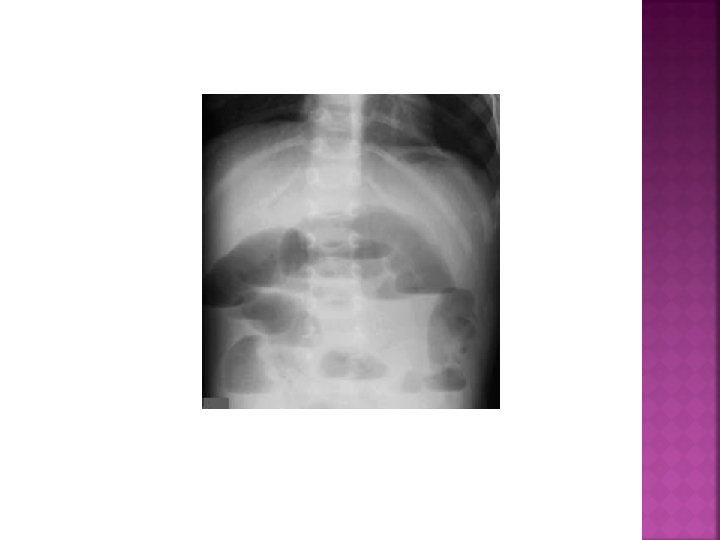

LABORATUVAR Direkt grafi (Fekalit, sağ alt kadranda hava sıvı seviyesi, Psoas gölgesi silinebilir, skolyoz)

AKUT APANDİSİT